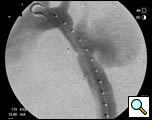

Selective angiography of the left subclavian artery was performed to confirm an intact posterior cerebral circulation. The proximal left subclavian artery was occluded with two 10mm Amplatzer vascular plugs which were introduced via the left external iliac sheath. An angiogram of the distal aortic arch and descending thoracic aorta was then performed to obtain a roadmap of the proximal and distal landing zones (Figure 4).